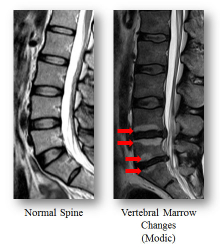

腰痛是本港勞動人口中常見的健康問題和請病假的原因,對社會造成沉重的經濟和醫療負擔。許多患有腰痛的人均曾嘗試過許多不同的治療方法,但結果並不理想。香港大學李嘉誠醫學院矯形及創傷外科學系自2001年起一直進行大規模的磁力共振掃描(MRI)人群研究,發現一種被稱為「Modic異變」的脊椎椎骨體變化,與椎間盤退變高度相關。這一突破性研究通過磁力共振檢查Modic異變來識別腰痛的根源已在《Medicine》的最新一期醫學期刊發表(http://journals.lww.com/md-journal/Fulltext/2016/05310/Refined_Phenotyping_of_Modic_Changes__Imaging.5.aspx )。

港大的大規模人口基礎研究為1,142名隨機抽樣的香港市民進行了磁力共振掃描,評估各種脊骨退化,如各類椎骨體上的異變、椎間盤退化、椎間盤突出等,並以這些影像數據評定其與不同程度的腰痛和殘疾的關聯性。

是次研究對象平均年齡為53歲,63%為女性。其中282(24.7%)名參與者有Modic異變,7.1%屬於I型(椎骨終板異常及骨髓內血管纖維化和水腫),另17.6%屬於Ⅱ型 (椎骨終板異常及骨髓內脂肪細胞滲透)。 Modic異變患者年齡較大,而且比沒有Modic 異變的人士有更嚴重的椎間盤退變和椎間盤突出。在調整偏差和個別影響因素後,研究人員發現各類的Modic異變均與長期嚴重的腰痛有關聯。 I型的Modic異變患者比II型的患者有更嚴重的疼痛,而II型的Modic異變則與下肢麻痹無力等殘障相關聯。疼痛和殘障的風險和嚴重程度均隨著Modic異變範圍和受影響的椎體數量而增加。

這是全球首個最大規模評估不同Modic異變的臨床研究。研究結果顯示Modic異變與長期嚴重腰痛和下肢殘疾有直接關係,磁力共振顯示的脊骨影像將可用作診斷腰痛的關鍵指標,透過脊骨上顯示的Modic異變形態和受影響範圍,醫生可得知個別病人的腰痛的成因和嚴重程度,並為病人訂立更完善和個人化的治療方案。這項研究將很大程度地協助醫生作出準確的臨床評估和判斷。